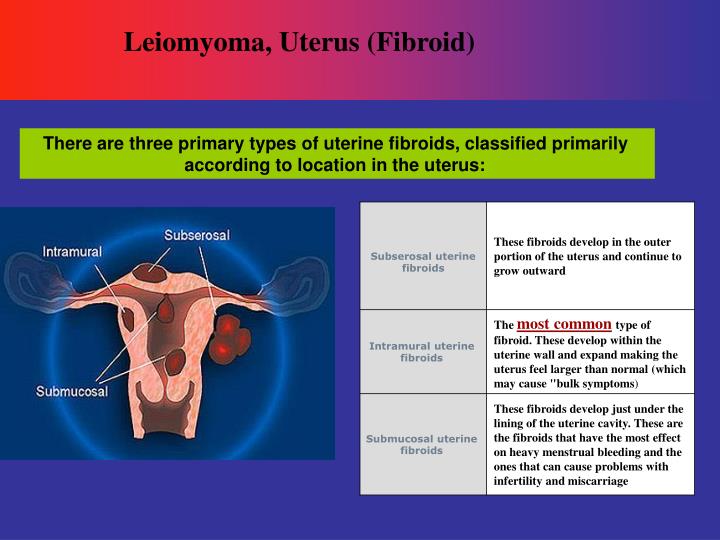

PPT - Leiomyoma, Uterus (Fibroid) PowerPoint Presentation - ID:862850

www.slideserve.com

www.slideserve.com

leiomyoma fibroid uterine uterus types fibroids ppt location primary three there leiomyomas powerpoint presentation multiple classified primarily according most slideserve